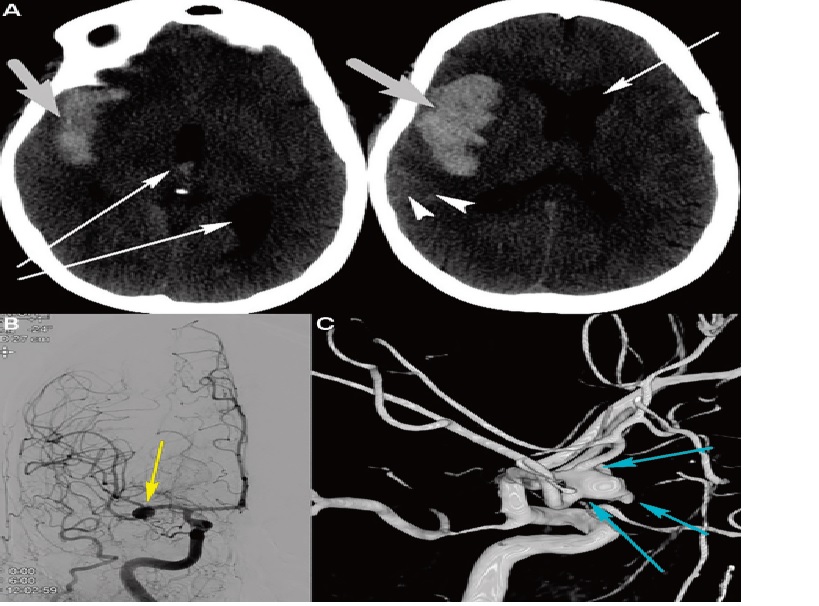

Ruptured right middle cerebral artery aneurysm requiring clipping, and subsequent cerebral vasospasm and delayed cerebral ischemia, A, Noncontrast head CT shows a large intraparenchymal component (thick arrows), small subarachnoid hemorrhage (arrowheads), and intraventricular hemorrhage with hydrocephalus (thin arrows). B, Cerebral angiogram reveals a right middle cerebral artery aneurysm (yellow arrow) as the culprit of the hemorrhage. C, Three-dimensional cerebral angiogram shows the complicated anatomy of this middle cerebral artery aneurysm with multiple vessels coming off the aneurysm and areas of irregular outpouching (blue arrows).

Nhận xét: Trường hợp này cho thấy bệnh nhân có chỉ định phẫu thuật (surgical clipping ) do vị trí nông của phình động mạch ở phần xa động mạch não giữa và giải phẫu của phình động mạch với nhiều mạch thoát ra khỏi phình mạch. Nó cũng cho thấy bệnh nhân có máu tụ lớn ở thái dương (có hoặc không có xuất huyết dưới nhện), phải có chẩn đoán hình ảnh mạch máu, vì phình động mạch não giữa có thể là thủ phạm.